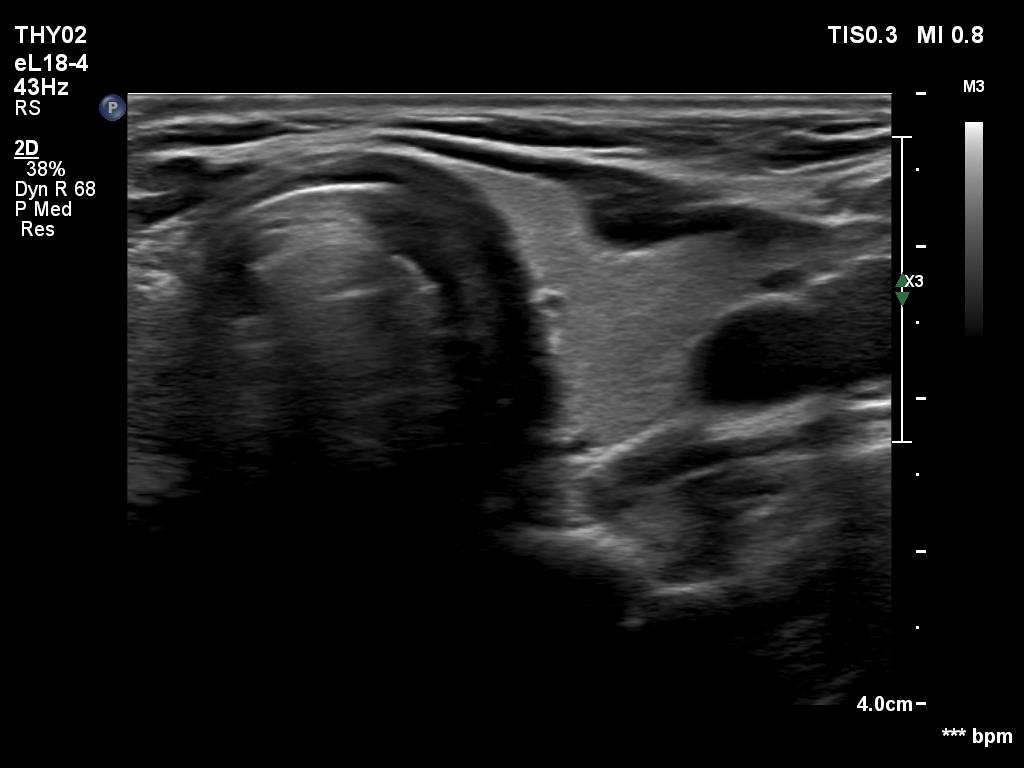

Elastography - case 1703 (ultrasonographic picture 6)

Lef lobe, transverse scan. This lobe is intact.